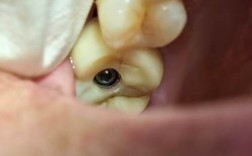

备洞与植入植体

备洞是技术要求最高的步骤,视频中医生使用种植机配套的系列钻头(从2mm引导钻到最终成形钻),逐级扩大窝洞,每更换一次钻头,视频中会特写钻头的直径和长度标记,医生会通过控制转速(前牙区800-1000rpm,后牙区400-600rpm)和持续用生理盐水冲洗降温,避免骨灼伤,当窝洞深度达到预定值后,医生用扭矩扳手测试骨密度(若骨密度低,可能需要攻丝),随后将植体旋入窝洞,植入时保持轻柔压力,避免用力过猛导致骨裂,视频中常展示植体植入后的初期稳定性(即植体在骨内无晃动),这是骨结合成功的关键。